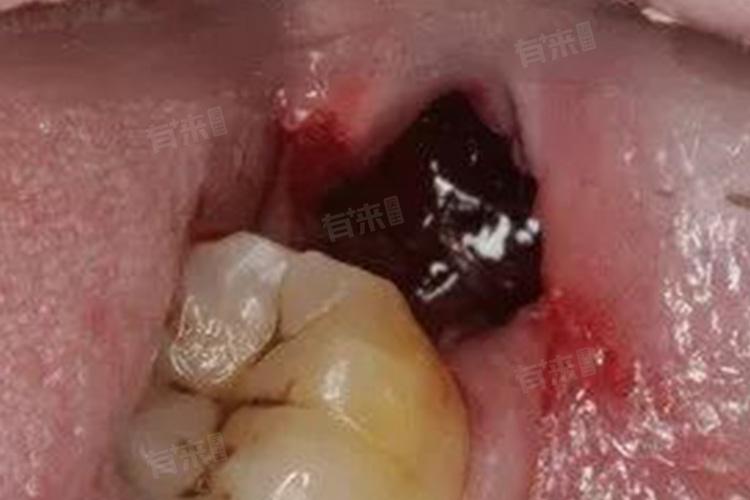

2、创口异常:拔牙创口内原本形成的血凝块脱落或溶解消失,牙槽骨壁暴露。创口周围牙龈红肿,触碰时疼痛加剧。正常情况下,拔牙创口会逐渐愈合,而干槽症患者的创口愈合缓慢,甚至长时间不愈合,严重影响患者的日常生活。